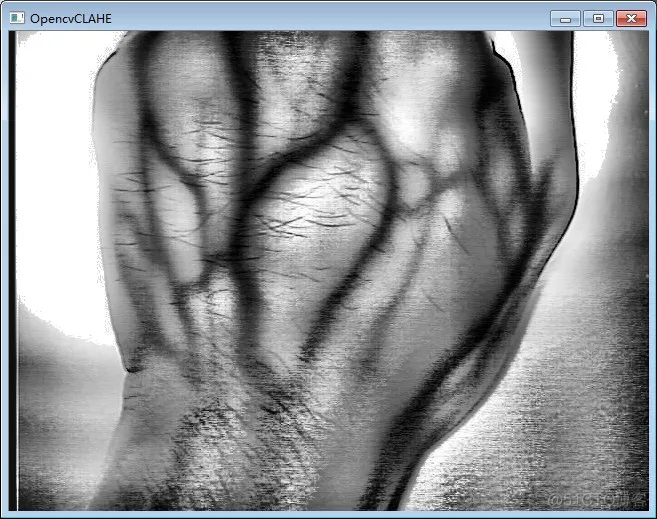

🌸CLAHE算法的应用:对于医学图像,特别是医学红外图像的增强效果非常明显:这篇博客做出了非常详细的讲解👉🏻CLAHE的实现和研究

这里放两张出自这篇博客的对比图感受一下: